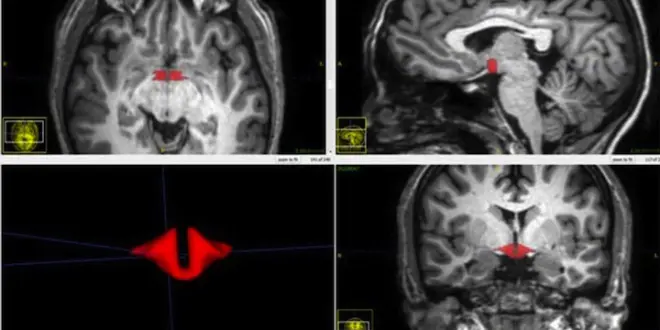

En rouge : l'hypothalamus, plus petit chez les femmes qui prennent la pilule.

En rouge : l'hypothalamus, plus petit chez les femmes qui prennent la pilule.  —  Crédits Photo : © RSNA / Dr M. Lipton

Quel est l’effet de la pilule contraceptive… sur le cerveau des femmes ? Des chercheurs du centre de recherche Gruss Magnetic Resonance de l’université de médecine Albert Einstein à New-York (Etats-Unis), ont présenté leurs derniers travaux sur le sujet au congrès annuel de la Radiological Society of North America (RSNA). Selon eux, les femmes qui prennent la pilule présentent un hypothalamus plus petit que les autres.

Pour leurs travaux, les chercheurs ont fait appel à 50 femmes en bonne santé, dont 21 prenaient une pilule contraceptive. Toutes ces volontaires ont passé une IRM du cerveau et les chercheurs ont calculé le volume de leur hypothalamus. "Nous avons constaté une différence spectaculaire dans la taille des structures cérébrales entre les femmes qui prenaient des contraceptifs oraux et les autres" déclare le docteur Michael Lipton, co-auteur de ces travaux, dans un communiqué de la RSNA.